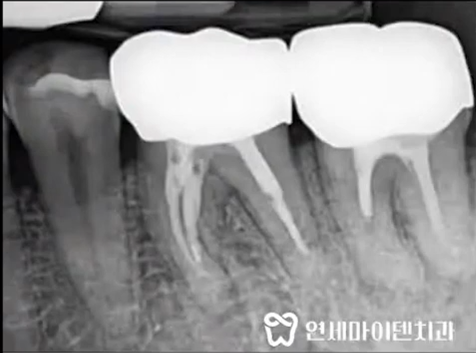

신경치료를 하지 않은 치아 안쪽에

검게 보이는 공간이 있습니다.

이곳이 바로 신경과 혈관이

지나가는 신경관입니다.